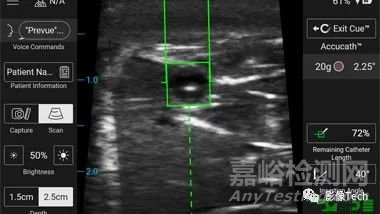

SiteRite™ 9 超聲系統(tǒng)是一款一體化系統(tǒng),采用更新后的 15.6 英寸觸摸屏,以提供用戶友好的體驗,具有增強(qiáng)的圖像質(zhì)量,提供行業(yè)領(lǐng)先的導(dǎo)管放置工具和技術(shù),在血管通路設(shè)備置入過程中為臨床醫(yī)生提供支持。該系統(tǒng)包括集成可視化工具,例如 Cue™ 針頭跟蹤系統(tǒng),為護(hù)理人員提供連續(xù)、實時的針頭位置跟蹤,以及 Sherlock 3CG+™ 尖端確認(rèn)系統(tǒng),用于在置入導(dǎo)管或針頭后,通過影像技術(shù)確保其準(zhǔn)確位置和定位。

SiteRite™ 9 系統(tǒng)還采用了智能互聯(lián)技術(shù),例如自動檢測血管的血管評估工具,可與血管測量工具配對,幫助臨床醫(yī)生選擇合適的導(dǎo)管,以便醫(yī)生每次都能做出明智的決策。其它系統(tǒng)功能包括通過信息捕獲進(jìn)行患者數(shù)據(jù)查找、自動填充和記錄傳輸,以優(yōu)化臨床醫(yī)生的工作流程。

SiteRite™ 9 超聲系統(tǒng)集成了 Sherlock 3CG+™ 尖端確認(rèn)系統(tǒng)(TCS),專用于血管通路,其可視化工具,可幫助醫(yī)生在 PICC 手術(shù)期間識別和測量血管。

支持設(shè)備選型

這款超聲系統(tǒng)將脈管系統(tǒng)的清晰可視化與實時測量相結(jié)合,可以幫助臨床醫(yī)生選擇最合適的血管通路裝置。該系統(tǒng)可自動檢測血管,然后應(yīng)用測量工具向臨床醫(yī)生提供有關(guān)導(dǎo)管與靜脈比率的信息,以滿足符合當(dāng)前 INS 標(biāo)準(zhǔn)的導(dǎo)管與靜脈比率規(guī)則。

針頭軌跡可視化

Cue™ 針頭跟蹤技術(shù)用于提供與目標(biāo)結(jié)構(gòu)相關(guān)的導(dǎo)針軌跡和針尖位置的視覺反饋。與“盲目”導(dǎo)管放置相比,實時可視化已被證明有助于減少醫(yī)生嘗試置入的次數(shù),從而改善患者的超聲引導(dǎo)針置入體驗。